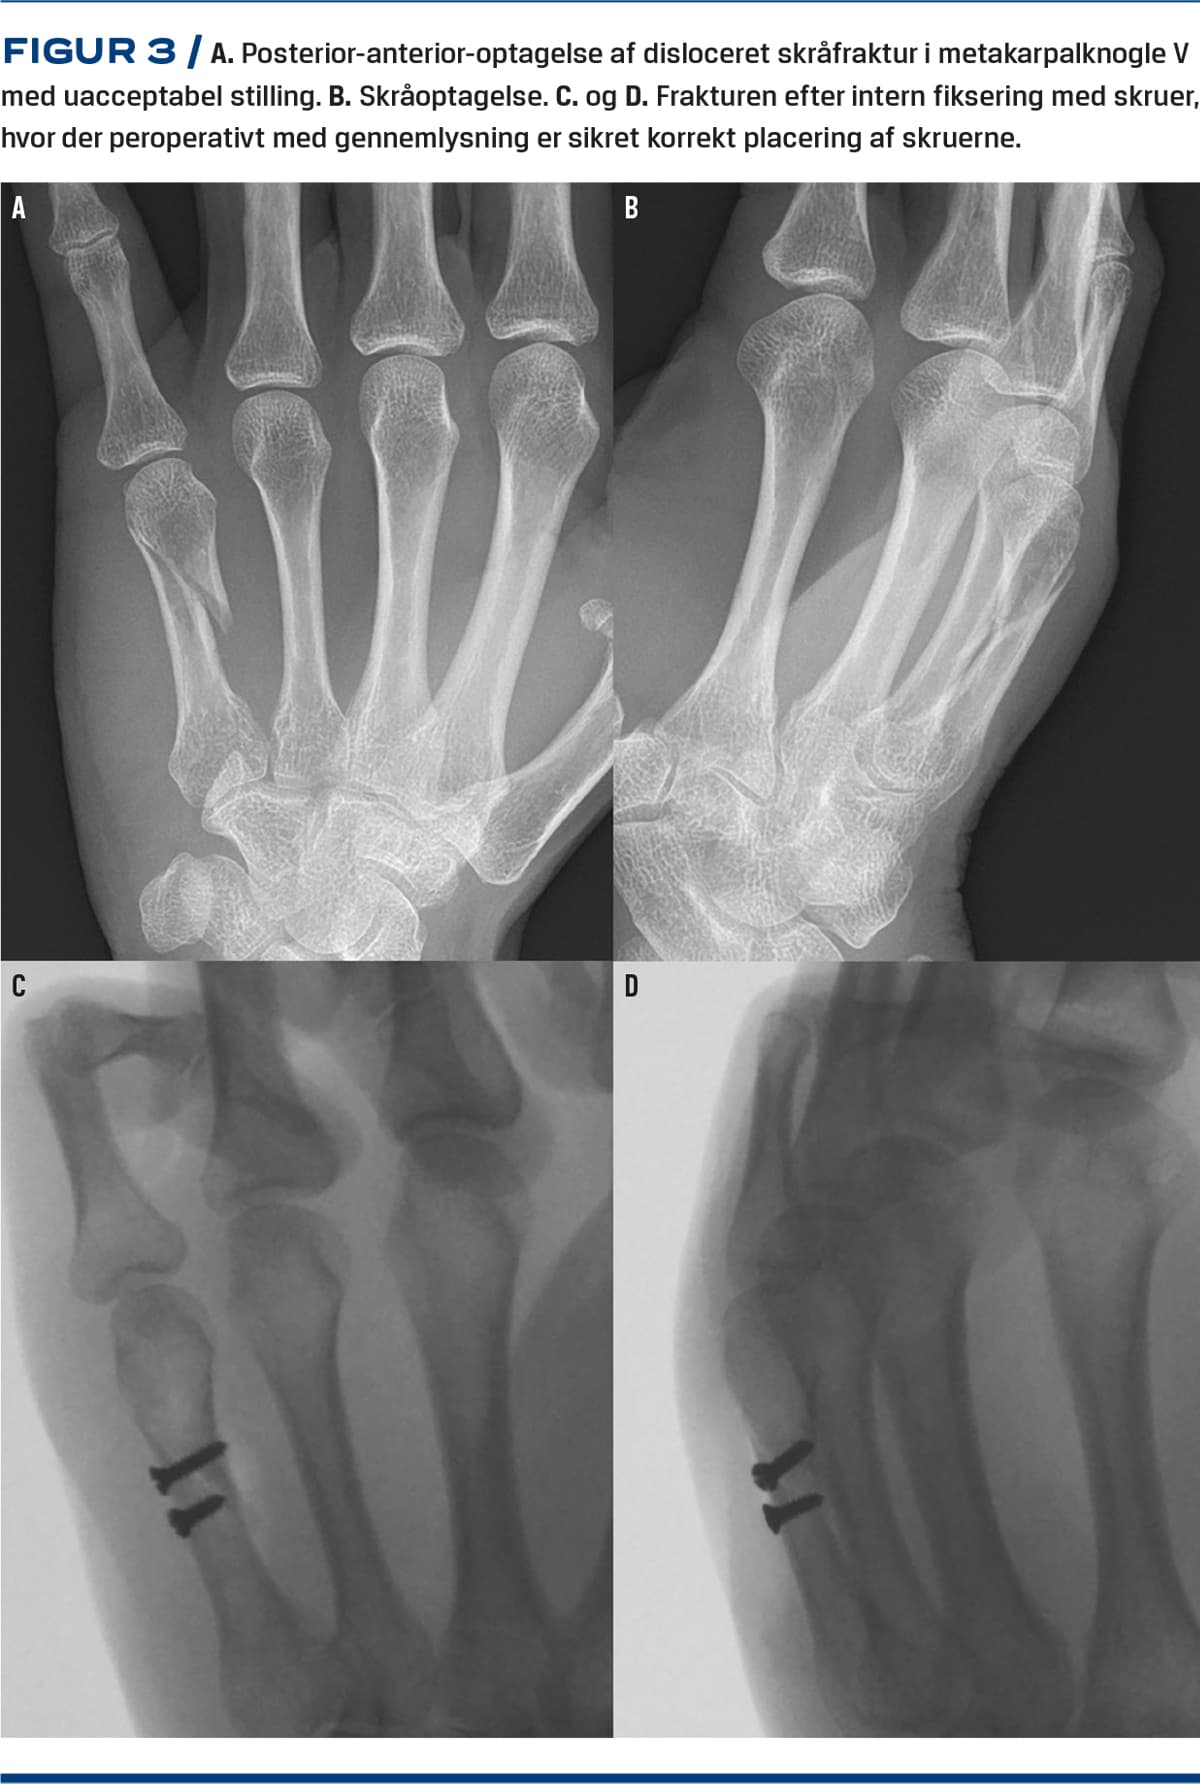

Udislocerede brud uden rotationsfejlstilling og dislocerede brud, der kan reponeres til tilfredsstillende stilling (Tabel 1), behandles med dorsalskinne/gips fra den øverste tredjedel af underarmen til knoerne og sambandagering til en rask nabofinger (f.eks. med buddy loop) i fire uger [19] eller med en funktionel bandage og tilsvarende sambandagering i tre uger [20-22]. Efter dette påbegyndes bevægeøvelser under sambandagering. Reposition af subkapitale frakturer udføres i lokalanalgesi med Jahss’ manøvre [23] (Figur 2). De maksimalt acceptable værdier for volar vinkling af subkapitale frakturer er angivet i Tabel 1. Hvis der ikke opnås tilfredsstillende reposition, anbefales brug af antegrad PCP eller ORIF (Figur 3) [24]. Skråfrakturer, avulsionsfrakturer, komminute frakturer og frakturer af multiple metakarpalknogler anses for at være ustabile og kræver ofte operation [4].